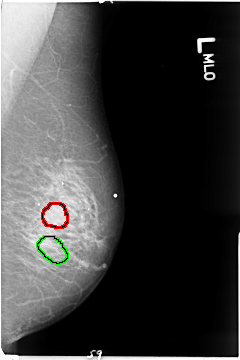

B_3043_1.LEFT_MLO

FILE: B_3043_1.LEFT_MLO.OVERLAY

TOTAL_ABNORMALITIES 2

ABNORMALITY 1

LESION_TYPE CALCIFICATION TYPE PLEOMORPHIC-FINE_LINEAR_BRANCHING DISTRIBUTION CLUSTERED-LINEAR

ASSESSMENT 4

SUBTLETY 3

PATHOLOGY MALIGNANT

TOTAL_OUTLINES 1

BOUNDARY

ABNORMALITY 2

LESION_TYPE MASS SHAPE ROUND MARGINS CIRCUMSCRIBED

ASSESSMENT 3

PATHOLOGY BENIGN